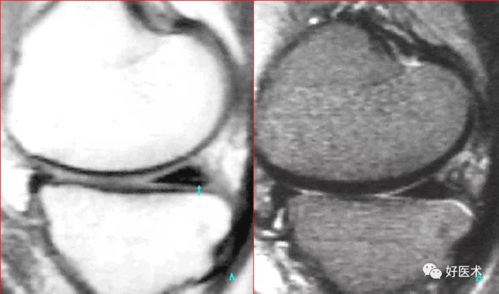

2、眼部检查:通过裂隙灯显微镜等设备,观察角膜的形态、炎症程度等。

4、影像学检查:如角膜地形图、角膜OCT等,评估角膜的厚度、曲率等。